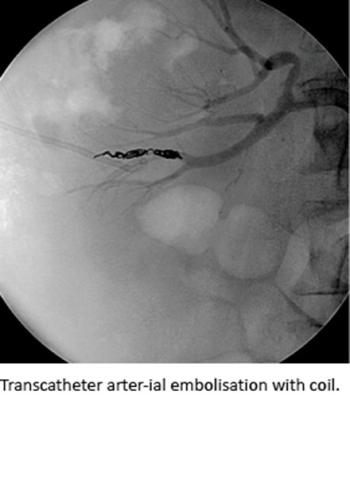

Trained interventional radiologists performed TAE in local analgesia via the common femoral artery. An initial renal angiography was obtained for identification of bleeding vessels and followed by embolisation if indicated and possible. The embolisation was performed

super-selectively to save as many nephrons as possible. The most common embolisation materials used were coils and vascular plugs; but in some cases of coagulopathy or patients on anticoagulation treatment, liquid embolisation materials were used. After TAE, the patients’ vitals was monitored closely and blood tests was taken specifically for post-embolisation complications at the Department of Urology. In elective cases, the patients’ co-morbidities and polypharmacy were optimised several days before the procedure. In the acute cases, all patients went directly to the theater without delay.